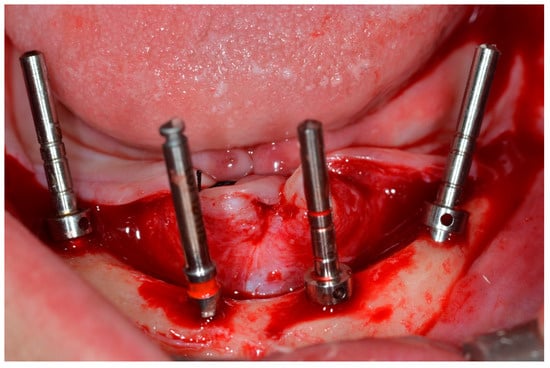

A supra-crestal incision was made in the first molar region, and two vertical releasing incisions were made in the first molar region. A mucoperiosteal flap was made and deflected, allowing the anatomical structures to be visualized [19] (Figure 3).

Figure 3.

View of the mandible after elevating the mucoperiosteal flap.

The drilling sequence for implant installation was performed according to the instructions of the implant manufacturer (Dérig, São Paulo, SP, Brazil), according to the All-on-Four protocol (Figure 4) [19,20,21].

Figure 4.

View of the mandible with parallel pins to check implant positions for the All-on-Four concept.

During bone instrumentation, when the surgeon’s experience enabled them to sense that the implant sites would have poor bone density, they performed sub-instrumentation to obtain the highest torque value possible at every site [10]. The surgeons decided this based on their extensive experience with All-on-Four treatments to promote lateral compression of the bone, thereby increasing primary stability [10]. The implants used in this study were tapered, with a rough surface, internal tri-channel connection implants (TRI Bioneck RP ∅ 4.3 mm, Dérig, São Paulo, Brazil) (Figure 5).